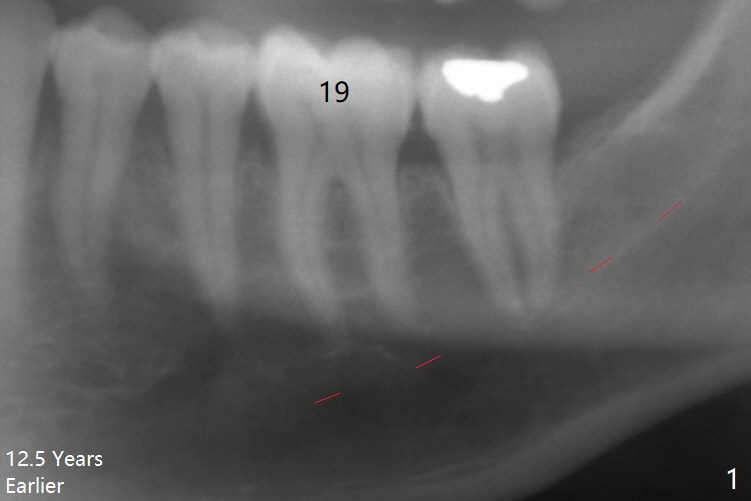

A 62-year-old man (smoker, 1.5 packs a day) has had no dental visit for 12.5 years (Fig.1). His chief complaint is pain at #19 after eating popcorn. The septal bone resorbes (Fig.2,3 *) with granulation tissue between the mesial and distal roots (Fig.4,5 *). Although there is no bony wall defect, the socket is single and large (9x9 mm, Fig.7). The largest (8 mm) cylindrical implant should not be able to obtain primary stability. The biggest challenge for immediate implant is ambiguous the Inferior Alveolar Canal (Fig.1,3 red dashed line). If there were no financial or time issue for immediate implant, CBCT should have been taken. Socket preservation is done instead with Vanilla graft, Human Amniotic Chorion Allograft (membrane) and Osteogen Plug (Fig.6). If he returns for SRP and implant, perform flapless bone expansion for osteotomy. When the patient returns 14 d postop, #19 socket is healing and filled with bone graft (Fig.8 (panoramic X-ray)). When he returns 14 months postop, the socket heals (Fig.9, as compared to Fig.6).